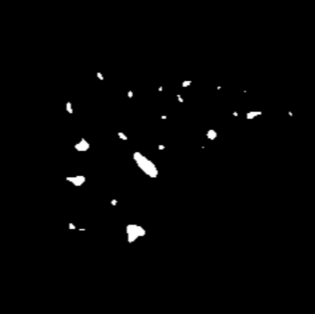

Manually segmenting the hepatic vessels from Computer Tomography (CT) is far more expertise-demanding and laborious than other structures due to the low-contrast and complex morphology of vessels, resulting in the extreme lack of high-quality labeled data. Without sufficient high-quality annotations, the usual data-driven learning-based approaches struggle with deficient training. On the other hand, directly introducing additional data with low-quality annotations may confuse the network, leading to undesirable performance degradation. To address this issue, we propose a novel mean-teacher-assisted confident learning framework to robustly exploit the noisy labeled data for the challenging hepatic vessel segmentation task. Specifically, with the adapted confident learning assisted by a third party, i.e., the weight-averaged teacher model, the noisy labels in the additional low-quality dataset can be transformed from "encumbrance" to "treasure" via progressive pixel-wise soft-correction, thus providing productive guidance. Extensive experiments using two public datasets demonstrate the superiority of the proposed framework as well as the effectiveness of each component.